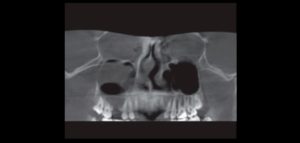

El número de pacientes que requieren prótesis sobre implantes ha aumentado considerablemente en los últimos años. La osteointegración de los implantes dentales es el requisito